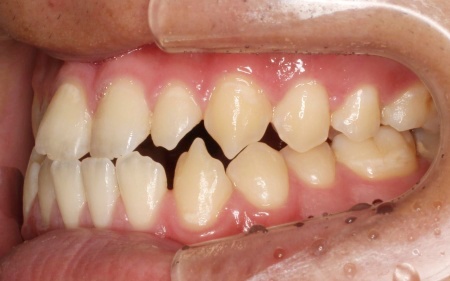

20代男性 受け口のように見える切端咬合をセラミックブラケットによる矯正治療で改善した症例

拝見したところ、上下前歯の先端同士が触れ合う「切端咬合(せったんこうごう)」の状態でした。

通常は上前歯が下前歯をわずかに覆うように重なりますが、患者様の場合は上下前歯の先端がほぼ同じ高さで噛み合っているため、受け口のような印象がみられました。

また、上下前歯の接触により下顎を前に出しにくく、後ろへ押し込まれやすい咬み合わせとなっています。

このまま放置すると、前歯の先端が少しずつすり減ったり欠けたりするリスクがあるだけでなく、顎の関節にも負担がかかり、食べ物を噛む機能や発音に影響が出るおそれもあります。

以上のことから、噛み合わせを改善をする必要があると診断しました。